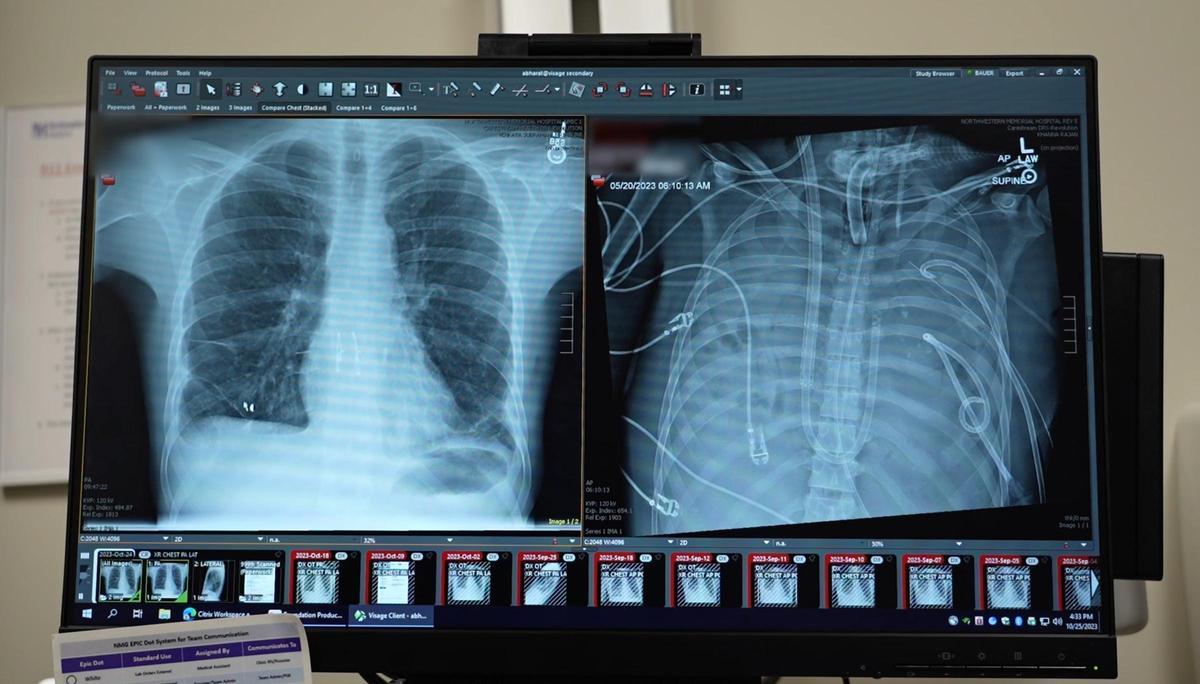

A la izquierda, imagen de los pulmones del paciente y a la derecha, muestra del órgano artificial implantado para mantenerlo con vida. / Northwestern Medicine

Un equipo médico de la Universidad Northwestern de Estados Unidos ha logrado salvar la vida de un hombre de 33 años con un fallo pulmonar irreversible gracias al uso de un sistema de pulmones artificiales. Según relatan los responsables de esta hazaña en un artículo publicado este jueves en la revista científica 'Cell Press', el uso de este órgano artificial permitió alargar la vida del paciente durante 48 horas hasta que, finalmente, se le pudo realizar un trasplante de pulmones. Los expertos afirman que esta estrategia clínica podría abrir nuevas posibilidades para personas que sufren daños multiorgánicos y que necesitan un salvavidas hasta la llegada de un trasplante.

Un equipo liderado por el cirujano torácico Ankit Bharat, del Northwestern Medical Group, optó por desarrollar un sistema extracorpóreo de pulmones artificiales. Según explica el doctor, a diferencia de otras herramientas de soporte desarrolladas para otros casos, en esta ocasión se diseñó un dispositivo capaz de, por un lado, oxigenar la sangre y eliminar el dióxido de carbono y, por otro lado, reemplazar funciones clave de la circulación pulmonar. De esta forma, afirman los médicos, se consiguió que el corazón siguiera bombeando sangre de forma estable pese a la ausencia completa de pulmones.

Gracias a este sistema, los cirujanos pudieron realizar una neumonectomía bilateral, es decir, una operación para extirpar ambos pulmones y eliminar así la fuente de la infección. Los médicos afirman que tras la cirugía el estado del paciente mejoró de forma notable, se estabilizó su presión arterial, disminuyó la necesidad de fármacos para mantener el corazón y otros órganos comenzaron a recuperarse. "El sistema de pulmón artificial lo mantuvo con vida durante dos días completos, hasta que aparecieron pulmones compatibles para el trasplante", comentan los médicos.